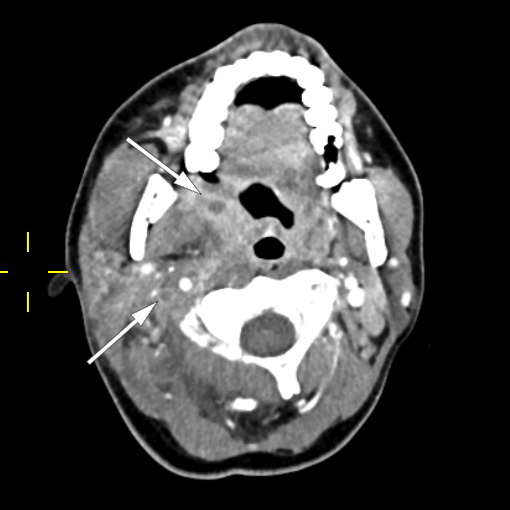

Pasienten ble videre undersøkt av vakthavende øre-nese-hals-lege. Man mistenkte abscedering, men trismus og smerter gjorde at det var vanskelig å få gjennomført en fullgod halsundersøkelse. Det ble derfor rekvirert CT collum. CT-funnene var forenlig med tonsillær/peritonsillær abscess bilateralt samt høyresidig trombosert vena jugularis med ledsagende tromboflebitt og flegmonøs betennelse (figur 1). På bakgrunn av dette ble Lemierres syndrom mistenkt. Abscessene ble vurdert som ikke modne for drenering, og det ble anbefalt bytte av antibiotika til klindamycin intravenøst, 600 mg × 3, hvilket ble startet opp neste dag. Grunnet trombosetendensen ble det også forordnet lavmolekylært heparin (enoksaparin), dosering 60 mg subkutant morgen og 40 mg subkutant kveld. P-piller (etinyløstradiol) ble seponert, da disse kan gi økt trombosetendens.

Pasienten fikk smerter i venstre del av toraks på dag 2. CT toraks og abdomen viste funn forenlig med septiske embolier i begge lunger og mulig infarktkomponent i høyre underlapp (figur 2, figur 3). I tillegg var det lett forstørret lever og milt, periportalt ødem samt små mengder fri væske i bekkenet (mulig fysiologisk). Det var også beskrevet mistanke om tromber i vena subclavia og vena axillaris på høyre side. Dag 3 så man oppvekst av penicillinfølsomme Streptococcus anginosus i blodkultur. Serologiske prøver viste svakt positivt Epstein-Barr-virus (EBV)-viralt kapsidantigen (VCA)-IgG, svakt positivt EBV-VCA-IgM og negativt EBV-EBNA-IgG. Intravenøst benzylpenicillin og klindamycin samt antikoagulasjonsbehandling med lavmolekylært heparin (enoksaparin) ble kontinuert.